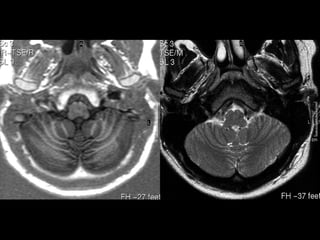

PONTE / BULBO

•   FORAME MAGNO

•   ART. VERTEBRAIS

•   TONSILAS CEREBELARES

•   CLIVUS                • VALÉCULA. FORAME DE

•   CANAL DO HIPOGLOSSO     MAGENDIE

• CISTERNAS

•   BULBO

• MAGNA

•   AMÍGDALAS

• PRÉ BULBAR

•   ART. VERTEBRAIS             • CEREBELO-BULBAR

•   BULBO JUGULAR         • PROTUBERÂNCIA OCCIPTAL